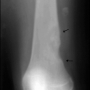

- Periosteal Osteosarkomlar

Kemik çevresindeki zardan kaynaklanan osteosarkom tipidir. Bu da sıklıkla düşük derecelidir ve emniyetli sınırlarla çıkartılması gereklidir.